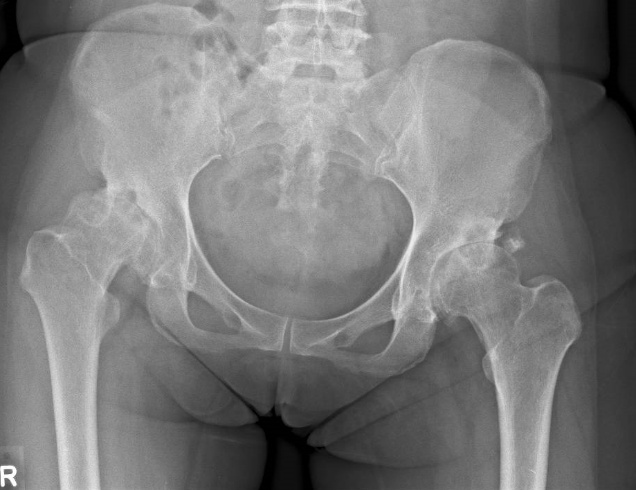

髋关节骨关节炎的发展阶段

OA分为四个阶段:

- 第1阶段(早期):轻微软骨磨损,无明显疼痛,常未被诊断。

- 第2阶段(轻度):骨刺形成,活动后偶发僵硬或疼痛。

- 第3阶段(中度):软骨明显侵蚀,频繁疼痛且活动受限。

- 第4阶段(重度):软骨几乎完全丧失,导致骨与骨直接摩擦、慢性疼痛、关节畸形,并可能出现股骨头变形(髋关节“球”状结构破坏)。